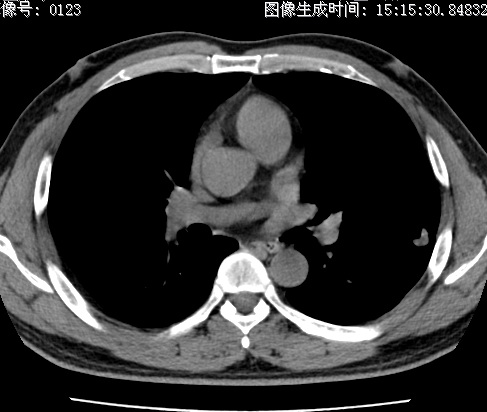

以下是引用zhao_bin2008在2010-1-4 20:15:00的发言:[br]先天性肺囊肿或小的肺隔离症?

以下是引用卜一在2010-1-4 22:09:00的发言:[br]先天性肺囊肿或小的肺隔离症?支持!

以下是引用zsl6918在2010-1-5 5:23:00的发言:[br]良性改变!肺囊肿,先天性支气管闭锁,血管畸形等均有可能。

以下是引用影像之路在2010-1-6 11:10:00的发言:[br]腺癌,最终的病检有些出乎意料之外,术前同志们大多考虑为肺囊肿或小的肺隔离征 [br]回过头来看 小结节呈分叶状,其内侧有一条较粗的静脉供血或许能成为支持诊断腺癌的理由